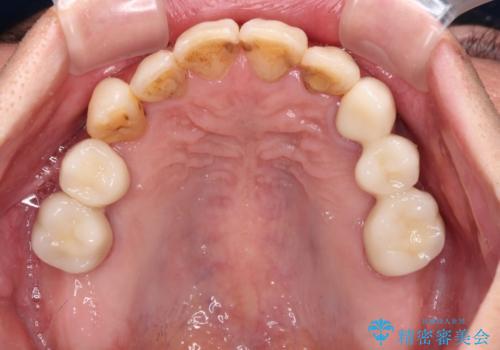

- 歯並びやグラグラする奥歯など、気になる所を全部治したいとのことで来院された患者様です。

奥歯は咬み合わせや歯周病により歯槽骨が失われていたり、むし歯や破折している歯などがあったりと、歯周病治療やインプラント補綴、矯正治療など、総合的に治療が必要と診断されました。

まずは歯周病治療やインプラント埋入を行い、環境が整った後にワイヤーを併用したインビザライン矯正を行い、オールセラミッククラウンにて補綴治療を行うこととしました。